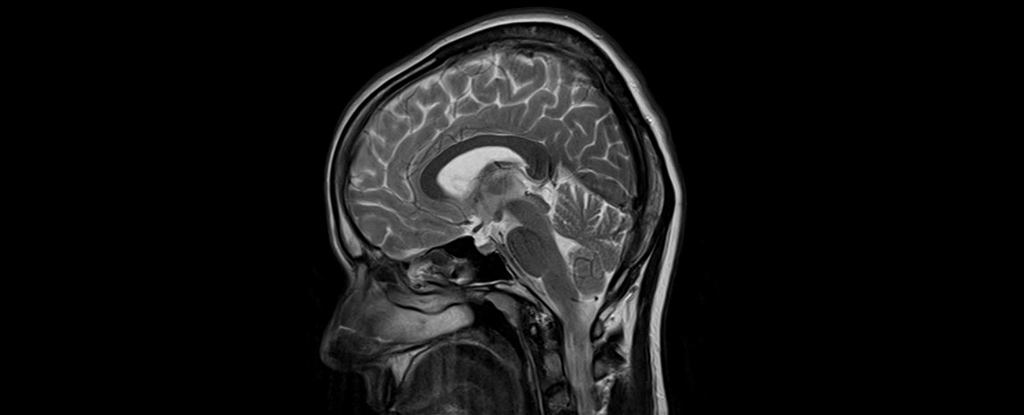

A global archive of over 4,400 preserved human brains, some dating back 12,000 years, has provided groundbreaking insight into soft tissue preservation, challenging the perception that naturally preserved brains are extremely rare. The brains, originating from various environments worldwide, were found to have been preserved through mechanisms such as dehydration, freezing, saponification, and tanning. This research could offer valuable information on human evolution, ancient health, and diseases, including neurodegenerative conditions like Alzheimer's. The study highlights the need for excavating archaeologists to remain open to unexpected discoveries and emphasizes the scientific value of studying these preserved human remains.